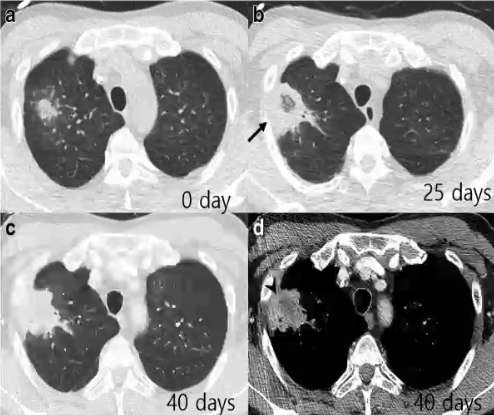

❖ 早期:实变、结节或肿块伴晕征

❖ 反晕征、中心坏死或空气新月征主要发生于治疗后粒缺恢复阶段